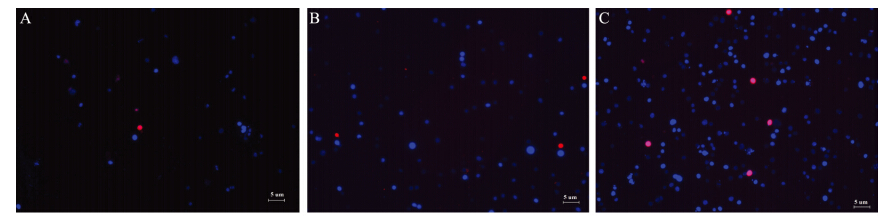

sorafenib作用EC9706细胞48 h后,同对照组相比,实验组(3 μmol/L组和6 μmol/L组)红染细胞增多,且随着药物浓度的增加,凋亡细胞明显增加(P<0.05),见图 2。

![]() |

| A: control group; B: 3μmol/L sorafenib group; C: 6μmol/L sorafenib group图 2 Hoechst/PI 染色阳性细胞(×100)Figure 2 Positive staining cells detected by Hoechst/PI(×100) |